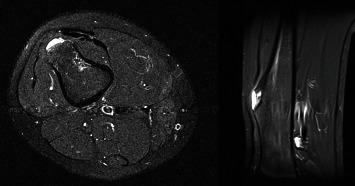

. Two pediatric patients presenting with benign bone tumors of the distal femur at the level of the suprapatellar fat pad developed late onset recurrent knee hemarthrosis following surgical treatment of the lesions. A sinus tract from the intramedullary bone to the knee capsule was discovered in both patients during surgical exploration. Resection of the sinus tract and full closure of the knee capsule resulted in no further recurrence. Postoperative knee effusions in patients following resection near the distal femur could represent hemarthrosis that require additional workup and treatment. Resection of the sinus tract successfully treats the hemarthrosis.

两名患有股骨远端良性骨肿瘤且肿瘤位于髌上脂肪垫水平的儿科患者,在病变接受手术治疗后出现迟发性复发性膝关节积血。在手术探查中,两名患者均发现从骨髓腔到膝关节囊的窦道。切除窦道并完全闭合膝关节囊后未再复发。股骨远端附近切除术后患者出现的膝关节积液可能代表积血,需要进一步检查和治疗。切除窦道成功治愈了积血。